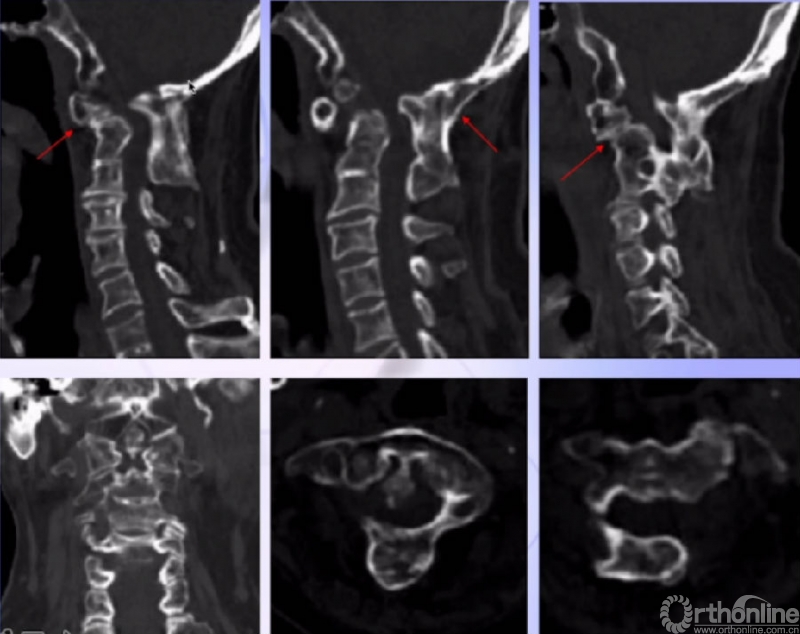

CT

1. 寰枢椎脱位

2. 枕颈融合术后

1. 神经内科

(1)延髓麻痹诊断成立;

(2)退变、压迫首先考虑;